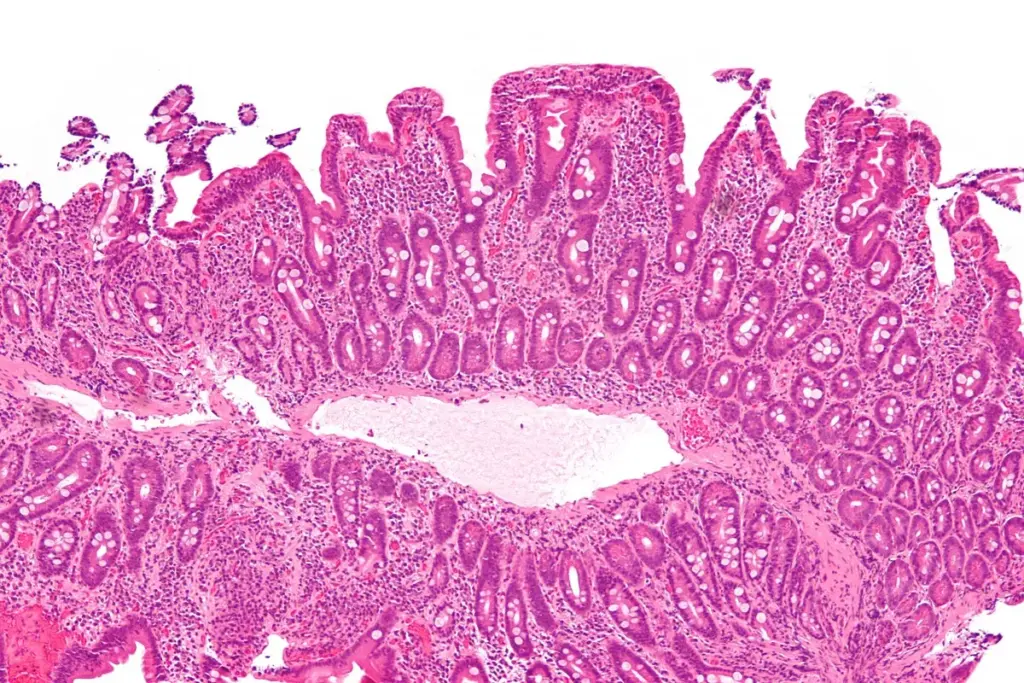

Celiac disease is an autoimmune disorder caused by gluten in people who are genetically predisposed. When people with celiac disease eat gluten, it triggers an immune reaction. This reaction damages the small intestine’s lining.

This damage can cause the body to not absorb nutrients well. This can lead to health problems.

Studies show that those with celiac disease who heal their intestines face less cancer risk. Intestinal healing means the small intestine’s lining is fixed. This is key because it helps the intestine work right, lowering cancer risk.

Healing the intestines is linked to sticking to a gluten-free diet. Avoiding gluten helps fix the intestine’s lining. This isn’t just about feeling better; it’s also about avoiding serious problems like cancer.